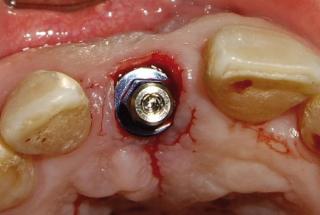

Clinical cases

MPI closely monitors clinical cases in the market to ensure their correct functioning and successful outcome.